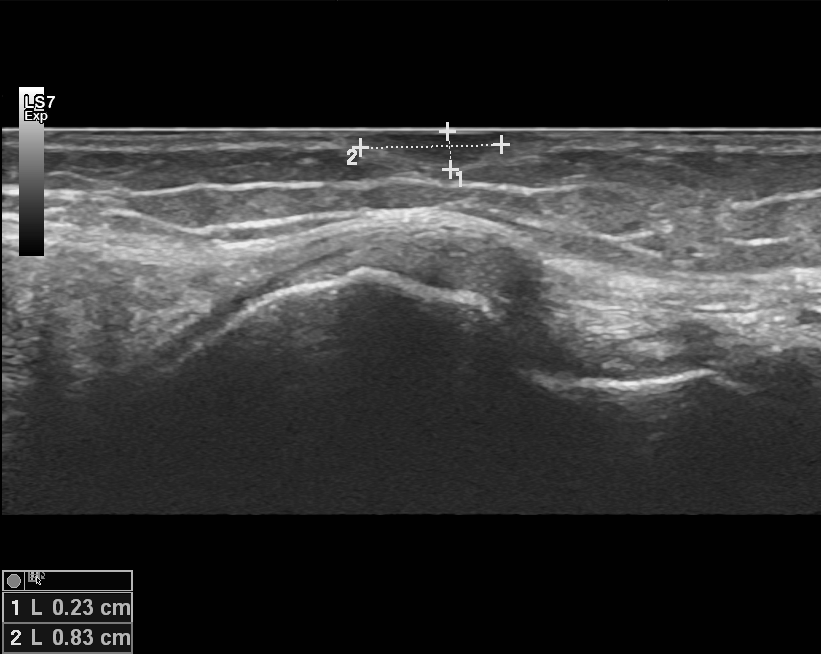

Ultraäänitutkimuksella voimme arvioida pinnallisten pattien luonnetta. Yleisimpiä syitä tulla ultraäänitutkimukseen ovat erilaiset iholla tuntuvat rasvapatit, suurentuneet imusolmukkeet ja nivelten alueella esiintyvät patit.

Mitä ultraäänitutkimuksella voidaan todeta

- Suurentuneet imusolmukkeet

- Rasvapatit

- Nivelten patit